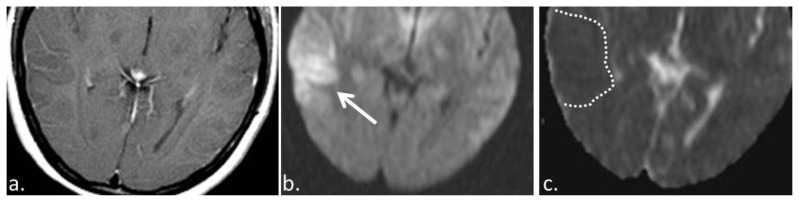

Figure 3.

19 year old female with anti-NMDA encephalitis. (a) T1 +C (3T MRI, TR 450, TE 30, post intravenous administration of 15 ml Optimark) axial image demonstrates no abnormal enhancement within the region of T2/FLAIR hyperintensity and gyral enlargement. (b) Diffusion weighted axial image (3 T MRI, TR 4000, TE 137) showing hyperintense signal in the right temporal lobe (solid arrow). (c) This region of DWI hyperintensity is associated with hypointensity on the ADC images (3 T MRI, TR 4000, TE 137) (dashed line) which is compatible with diffusion restriction.

The initial CT of the brain was unremarkable with the areas of abnormality seen on the later MRIs appearing isodense to normal adjacent cortex. MRI demonstrated T2/FLAIR hyperintensity in the temporal lobe with corresponding low signal on T1 images and diffusion restriction on DWI/ADC. The MRI of our patient did not demonstrate abnormal contrast enhancement which is consistent with imaging descriptions in the literature. Furthermore, no frank or petechial hemorrhage was identified.